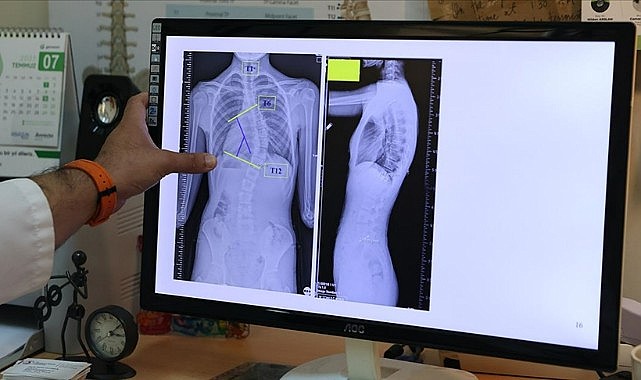

Doç. Dr. Coşkun, AA muhabirine, omurganın ön ve arka planında 10 dereceden fazla olan eğriliği skolyoz hastalığı olarak kabul ettiklerini belirtti.

Skolyozun duruş bozukluğundan ayırt edilmesi gerektiğini vurgulayan Coşkun, duruş bozukluğunun basit egzersizlerle düzelebileceğini, skolyozda ise omurga yapısında bir deformasyondan söz ettiklerini anlattı.

Coşkun, skolyozun genellikle 10-19 yaş aralığında görüldüğüne işaret ederek, "Skolyoz, nedeni bilinmeyen bir hastalıktır. Ergenlik, adölesan idiopatik skolyozun en sık görülen yaş grubunu oluşturmakta. Şikayetler genelde omuzların bir tarafında yükseklik farkı olması, bir omuzun daha yukarıda yerleşmesi. Ayrıca hasta öne doğru eğildiğinde, hastada bir tarafında sırtında bir yükseklik, bir kamburluk bulgusu olması. Bu yükseltinin bir tarafta belirginleşme, diğer tarafta silinme, skolyozun ana bulgularındandır." dedi.

"Skolyoz hastalığında tedavilerden biri gözlem tedavisidir. Gözlem skolyozda bir tedavidir. Biz gerçekten de 0 ila 20 derece arasındaki eğriliklere pek bir şey yapmayız. Bu çocukların gelişimini takip ederiz ve erişkin yaşa geldiğinde de bu tedaviyi sonlandırırız. Artık bu çocukların bir riski, hastalığın ilerlemesi açısından yoktur. 20 ila 40 derece arasında ise ya da 45 dereceye kadar biz çocuğun yaşı eğer uygunsa korse tedavisi uygularız. Korse tedavisi için çocuğun büyümesinin devam etmesi lazım. Kemik yaşı tamamlan, büyümesi tamamlanmış bir çocukta korse tedavisinin yeri yoktur. 45 dereceyi aşan eğriliklerde ise eğriliğin her sene ilerleyeceğini öngörerek cerrahi tedavi uygulamaktayız."

Skolyozun özellikle kız çocuklarında daha sık görüldüğünün altını çizen Coşkun, ergenlik öncesi çekilecek bir omurga röntgeninin tedavide daha iyi yol alınmasını sağlayacağına işaret ederek, "Kız çocuklarında doğumsal kalça çıkığında olduğu gibi skolyoz yönünden tedbirli olmakta fayda var. Özellikle adet öncesi dönemde kızların en azından bir omurga röntgeninin çekilmesi, yine erkeklerde de ergenlik öncesi dönemde bir kez omurga röntgeninin çekilmesi olası bir skolyoz hastalığının tedavisine erken başlamak adına önemli. Çünkü tedaviye ne kadar erken başlarsak o kadar iyi sonuç alma ihtimalimiz yüksek." ifadelerini kullandı.